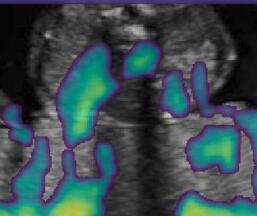

Fig. 6 compares the shadow confidence maps of the state-of-the-art methods and the proposed methods. RW and have the same parameters as used for Table I. The shadow confidence maps of the baseline, the proposed method and the proposedAG method are generated directly from input shadow images by confidence estimation networks. Overall, the proposed method and the proposedAG method achieve more visually reasonable shadow confidence estimation than the baseline and the state-of-the-art on different anatomical structures shown in Fig. 6. The proposed method and the proposedAG method are able to highlight multiple shadow regions while the RW algorithm shows limitations for most cases, especially for disjoint shadow regions.

Row I in Fig. 6 shows a fetal brain image from . The confidence estimation of shadow regions from the baseline, the proposed method and the proposedAG method are similarly accurate since we use fetal brain images to train the confidence estimation networks in these three methods. These outperform [16] and [22]. Rows (II-IV) in Fig. 6 show shadow confidence maps of non-brain anatomy from , including lips, abdominal and cardiac. The baseline failed on unseen data during inference. However, the proposed methods are able to generate accurate shadow confidence maps because of the generalized shadow features obtained by the shadow-seg module. Furthermore, the “Lips” example shows that our method is capable of detecting weaker shadow regions that have not been annotated in manual segmentation. This indicates that the confidence estimation network has learned general properties of shadow regions.